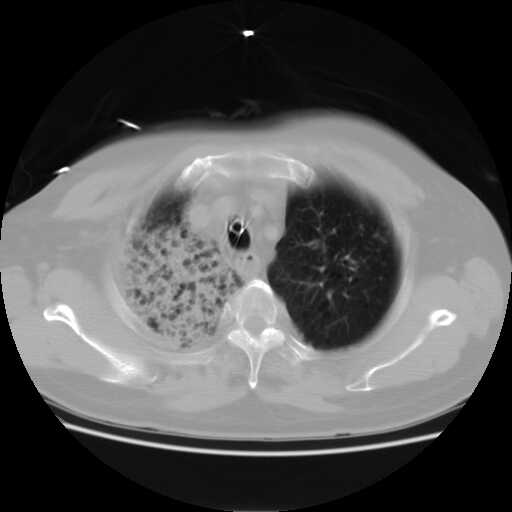

患者,男,60岁,病史如下:

2008.8.17ct

病变从8.11-8.17明显改变,增多,以蜂窝状改变为主,类蜂窝肺,似弥漫性肺泡癌,但是病变进展太快,不符合弥漫性细支气管肺泡癌。因此考虑为特殊微生物感染,多以霉菌类常见,建议细菌微生物学检查。

疑点二:影象表现怪异,大片阴影内见多发筛孔征,如何解释.

间质为主,血管炎性水肿?

军团杆菌肺炎ct表现无特意性,主要—两肺浸润性 弥漫性病变,并少量胸腔积液。